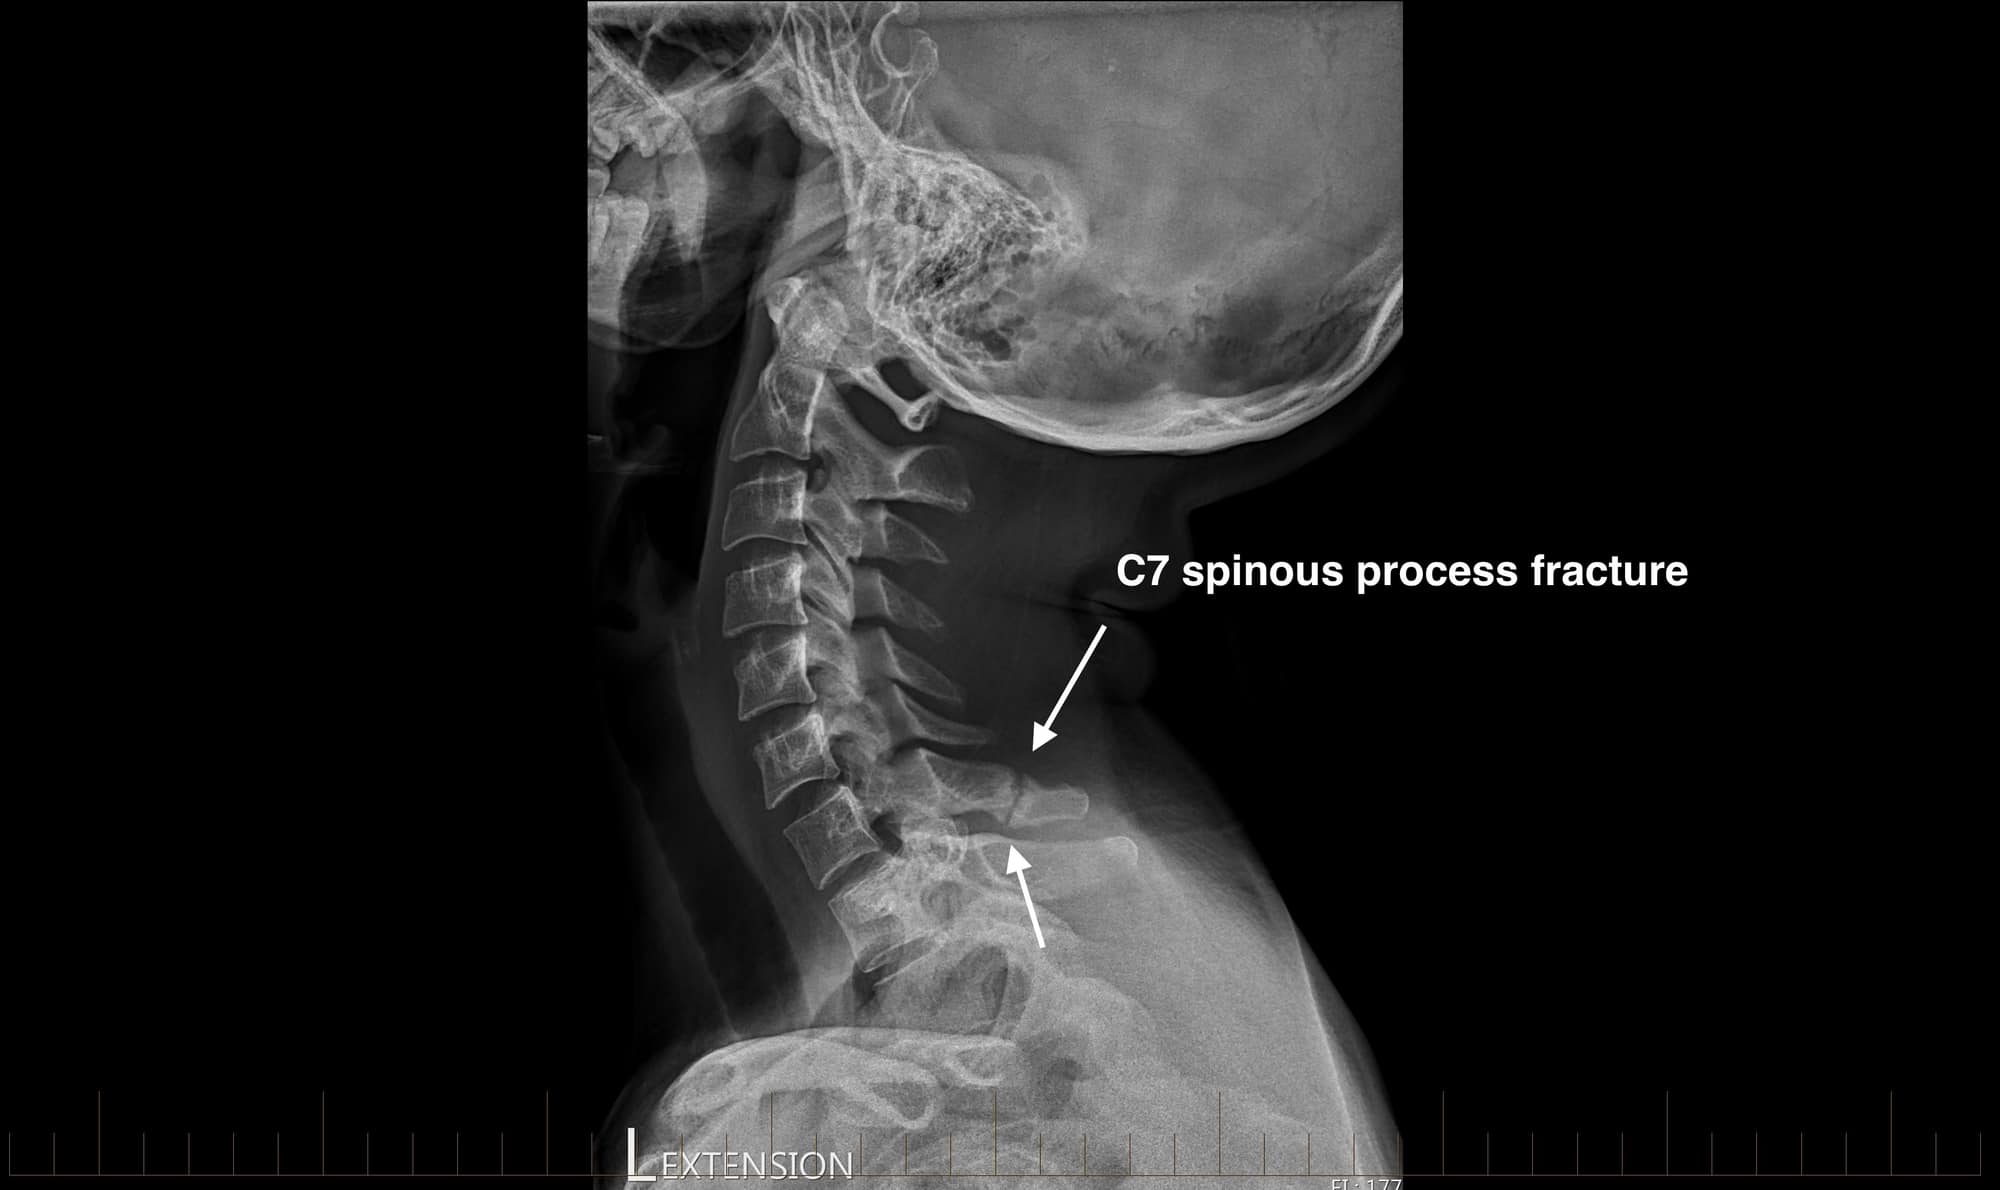

From www.axissportsmedicine.co.nz

Radiology Review C7 Spinous Process Fracture Axis Sports Med Spinal Cord Compression X Ray When the spinal cord compresses, it. Spinal cord compression (scc) is a surgical emergency, usually requiring prompt surgical decompression to prevent permanent. Mri scans create images of the. Symptoms of spinal cord compression include pain, loss of. Spinal cord compression results from back injuries or conditions that gradually compress the spinal cord over time. Severe compression of the spinal cord. Spinal Cord Compression X Ray.